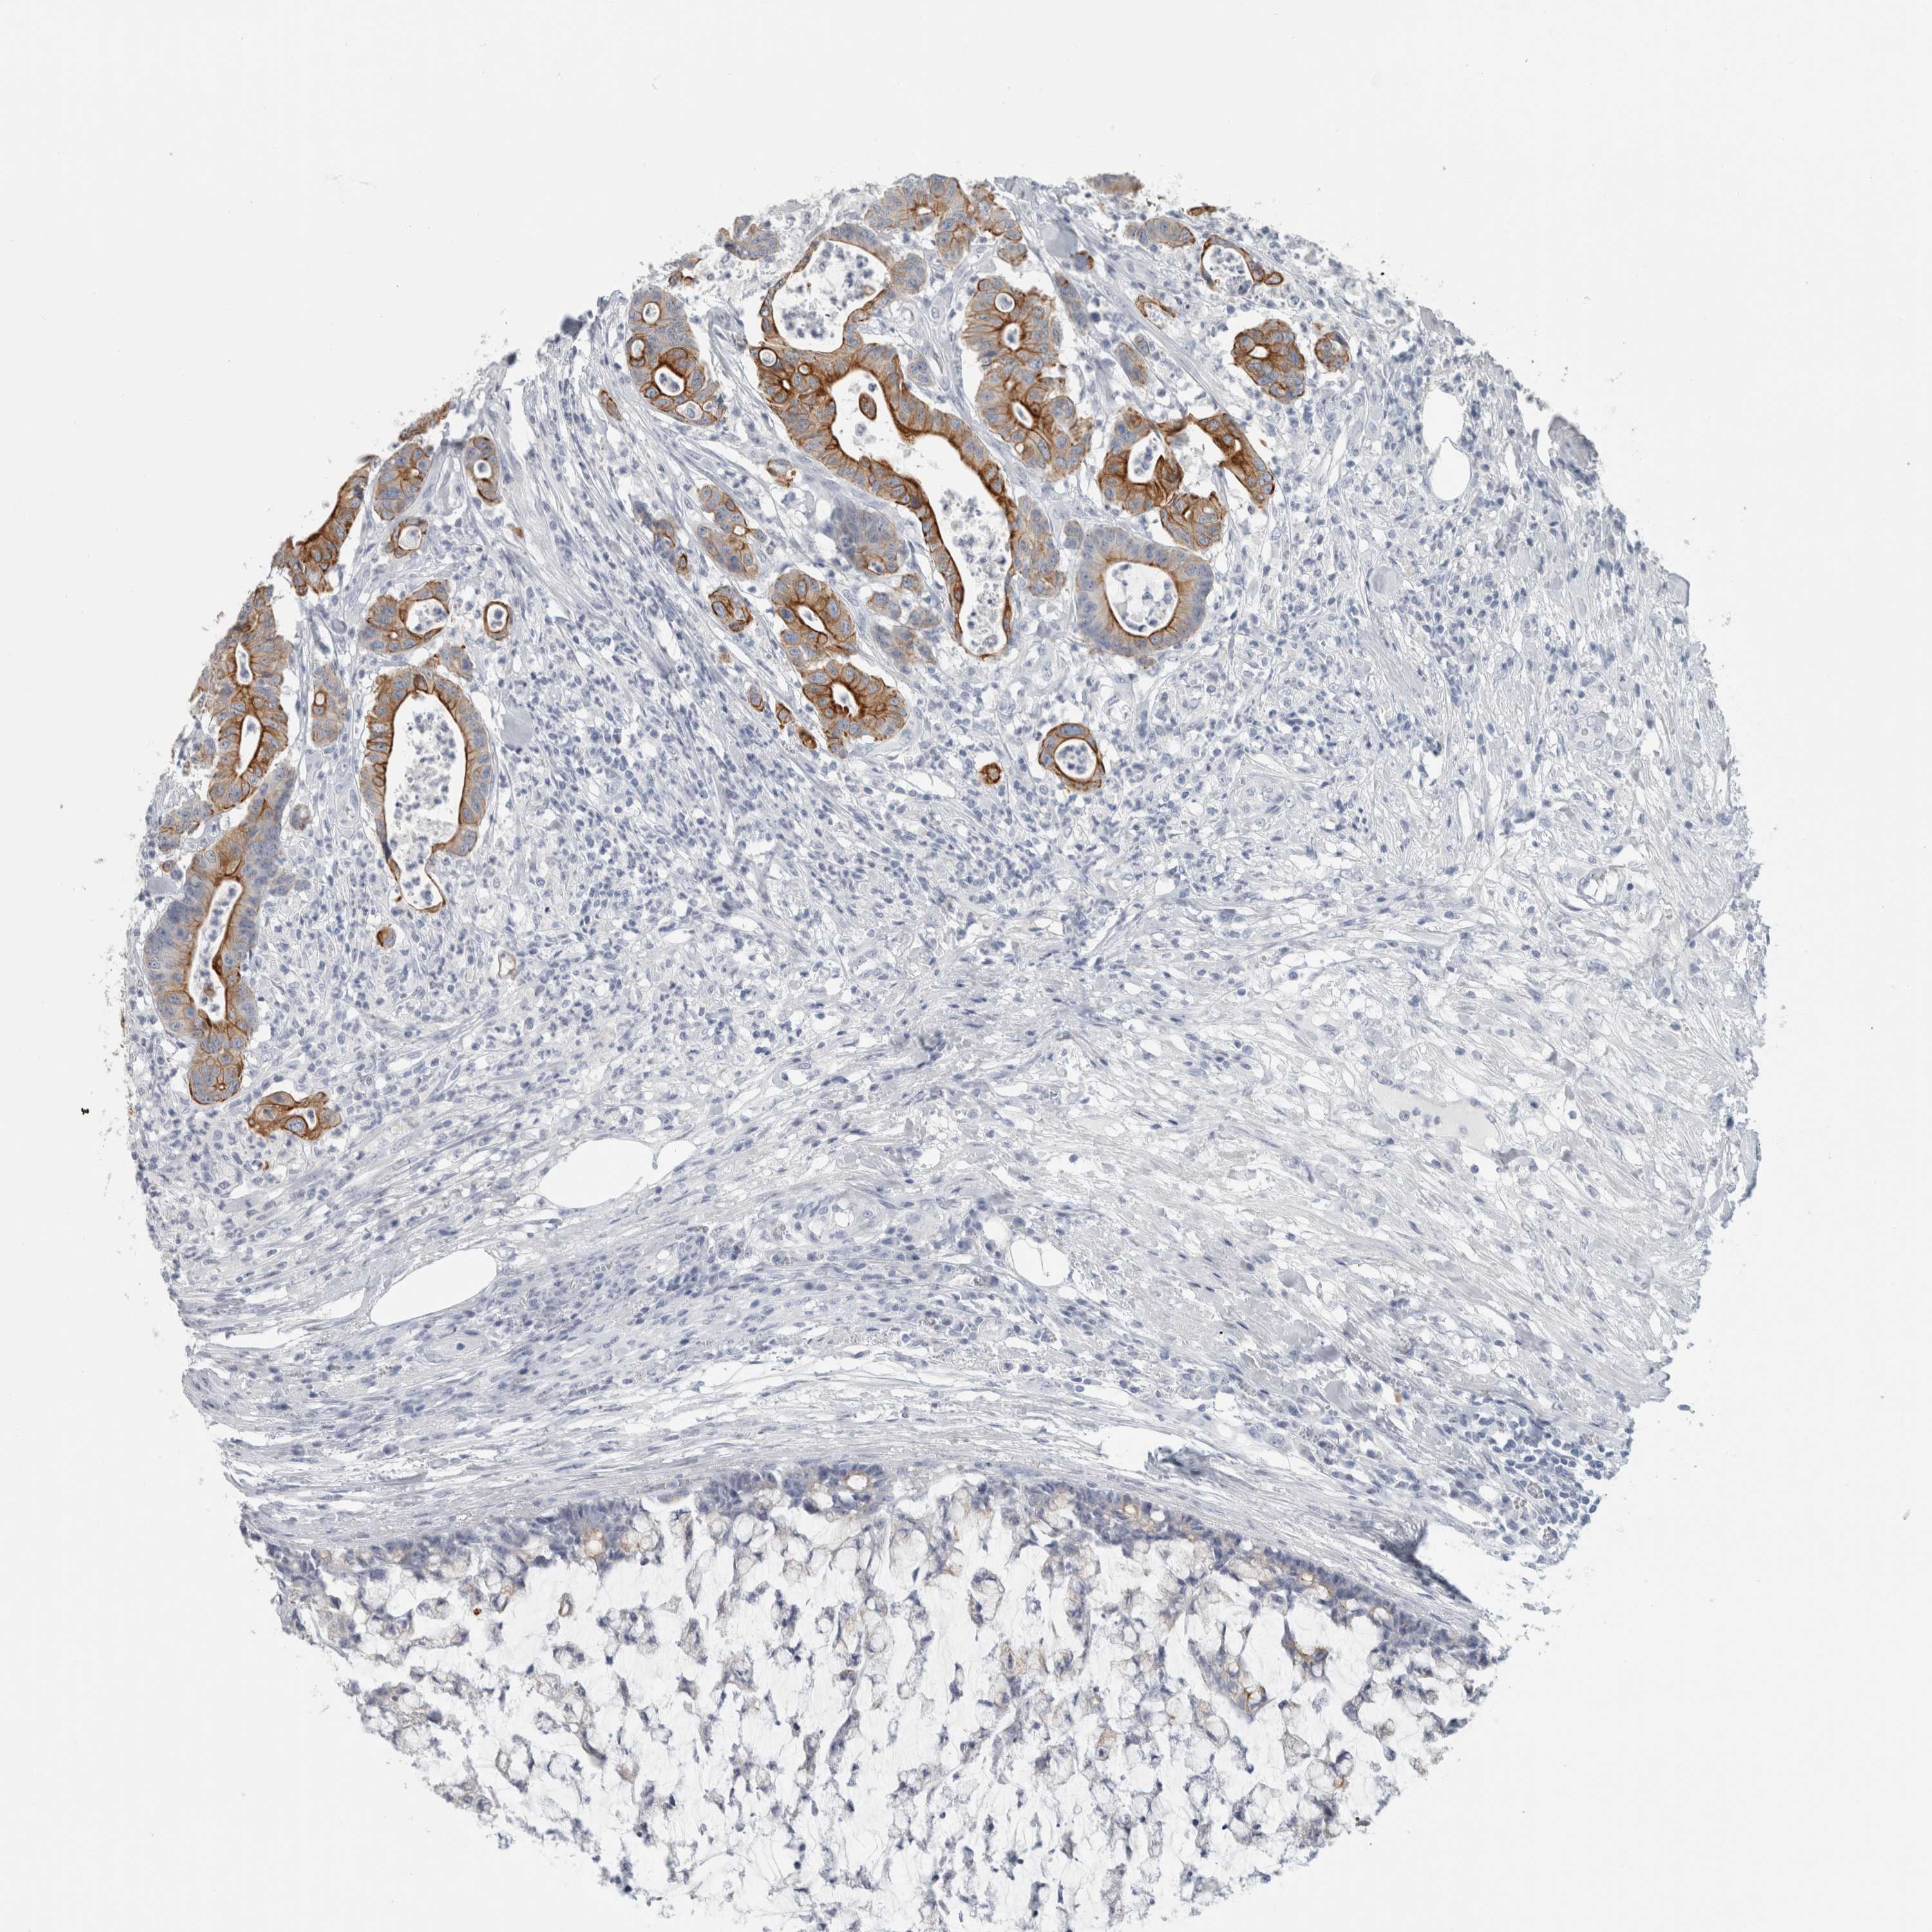

CANCER COLORECTAL CANCER Show tissue menu

Colorectal cancer

Human cancer

Colon adenocarcinoma